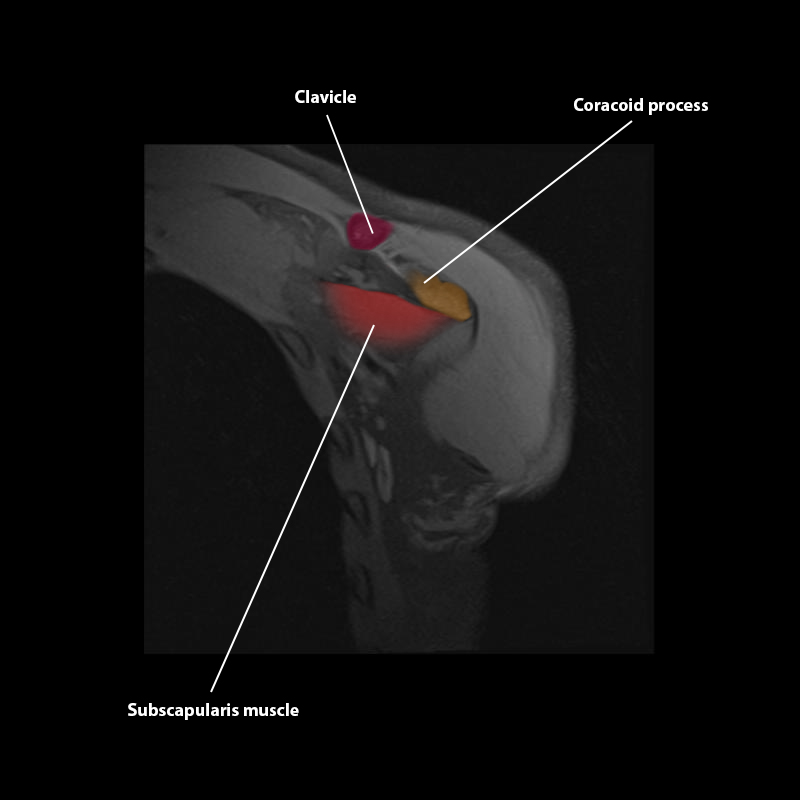

Shoulder MRI Anatomy